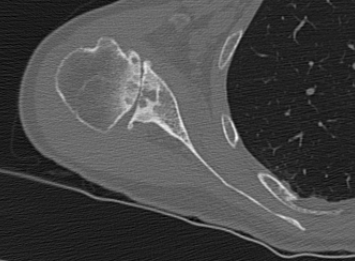

Chalmers et al. J Should Elbow Surg 2017

- 14 B2 glenoids

- glenoid version measurement accurate if > 50% of the scapula width included